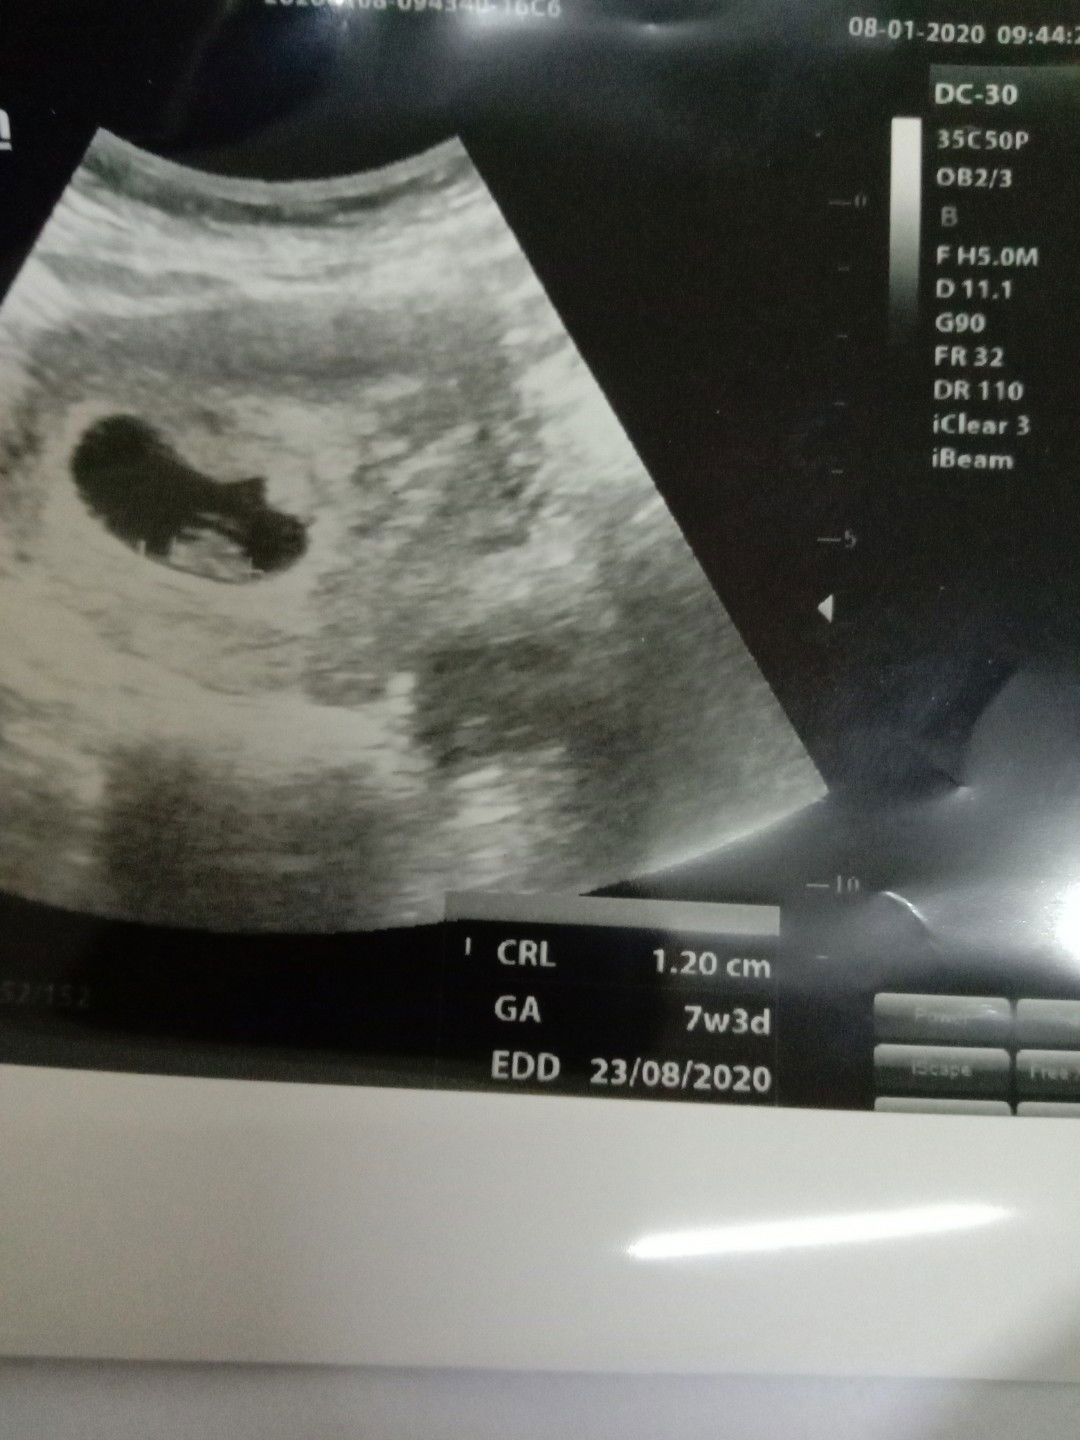

belum terdeteksi detak jantung

Bun,sy diperiksa usia kandingn 7w3h Kantung dan janinya sdh terlihat tp detak jantung belum terdeteksi Kira2 gimana ya bunda2 yg lain